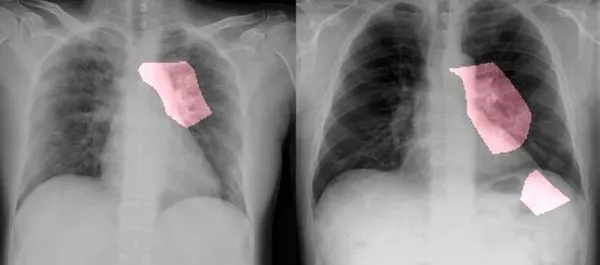

Dünya Sağlık Örgütü uzmanları, Covid-19 ile nikotin ilişkisini inceleyen araştırmaları gözden geçirdiklerini belirtti. Sigara içenlerde Covid-19 vakalarının daha ağır seyrettiğini söyleyen DSÖ yetkilileri Avrupa Hastalıkları Kontrol Merkezi'nin (ECDC) bildirisinde sigara içenlerin Covid-19'a karşı 'riskli gruptan' oldukları uyarısını da hatırlattı.